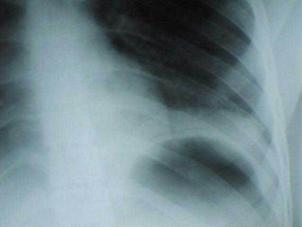

Contuzie pulmonara stanga Contuzie pulmonara dreapta

Contuzie pulmonara dreapta.Imagine CT